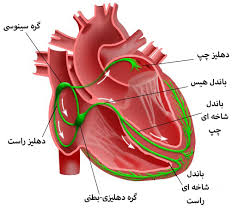

قیمت: 96٬000 تومان - دسته بندی فایل: پاورپوینتپاورپوینت آریتمی قلبی (ppt) 124 اسلاید

فروش ویژه پاورپوینت حرفه ای آریتمی قلبی / تعداد اسلاید: 124 اسلاید